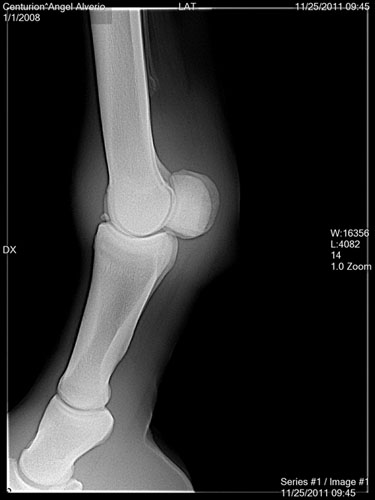

Thanks. Enclosed an X Ray ...

Angel, I do not see a medial condylar fracture in these views. I would expect such a fracture to be best seen in a ap (front to back) view rather than a lateral view like we have above. There is a rather significant piece of bone fragment, often called a joint mouse, seen in the first image above however. DrO